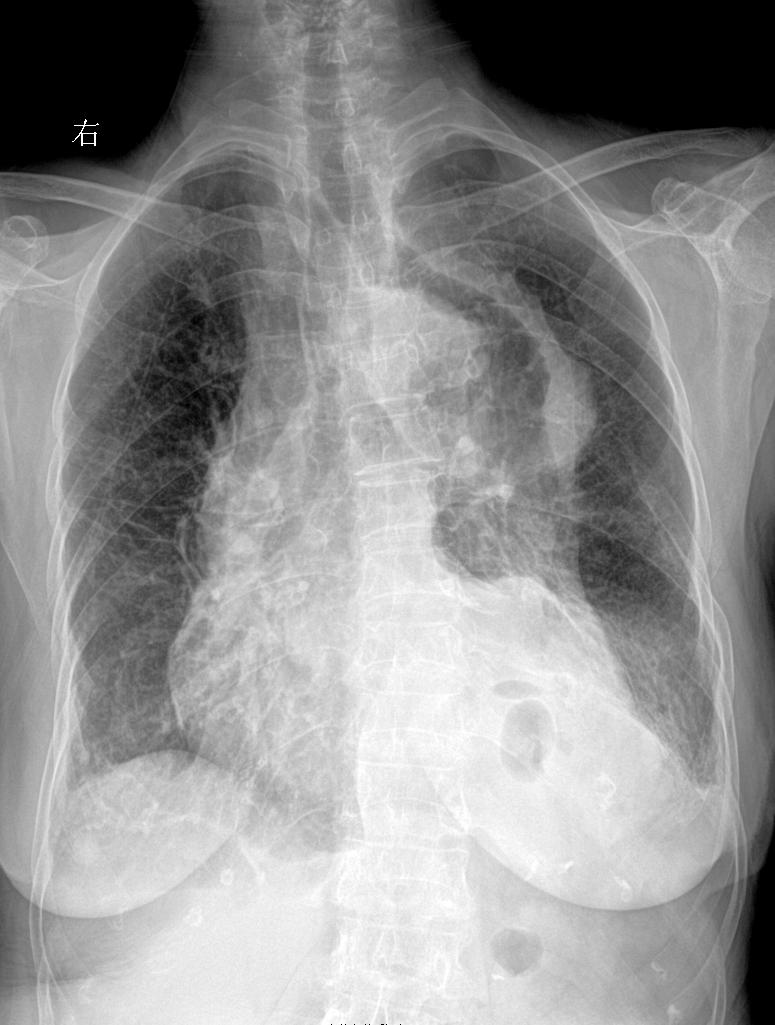

男 57y 咳嗽带红色痰 感冒胸闷就诊

上期被查封 重新发一下家人们 再来一起探讨下肺结核 胸部正位片